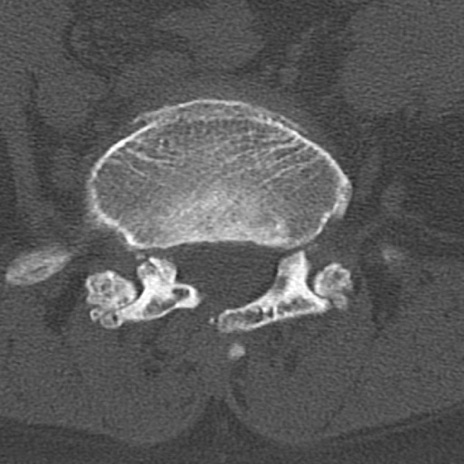

腰椎CT

横断像と矢状断像